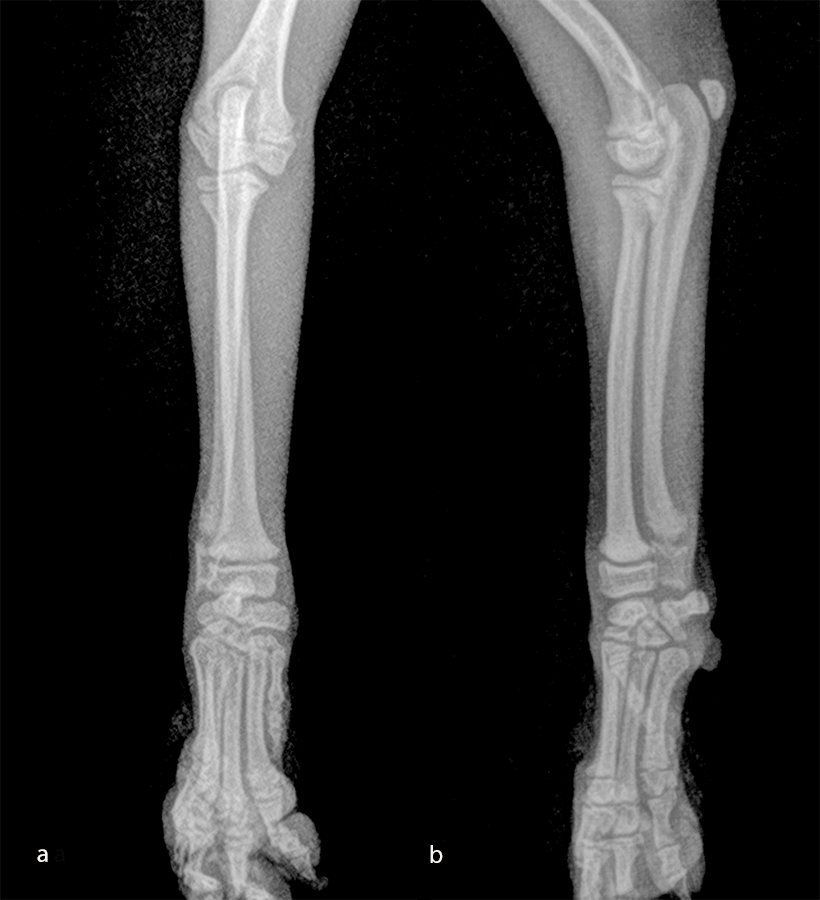

The patient was a 6-month-old, 1 kg (exactly 0.950 kg) Pomeranian dog presenting with a radial fracture of the left thoracic limb after a jump from ≈ 50 cm. The 1.5 mm System was too large for the width of the radius (2.2 mm) and the width of the radial medullary canal (0.5 mm) (Fig 7). The 1.3 mm adaptation plate was a perfect plate for this fracture. This plate option permitted the use of cortex and locking screws.